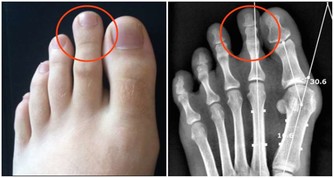

4厭油膩,小便發黃者需要養肝,主要是因為肝臟分泌和產生膽汁的功能減弱,使得肝臟對脂肪的消化功能減弱,因此會出現厭油膩的現象肝臟排泄膽汁受阻,血液中的膽紅素升高,過多的膽紅素經過腎臟排泄,就會出現小便發黃的現象,因此,出現這一症狀的人應該注意養肝調理。